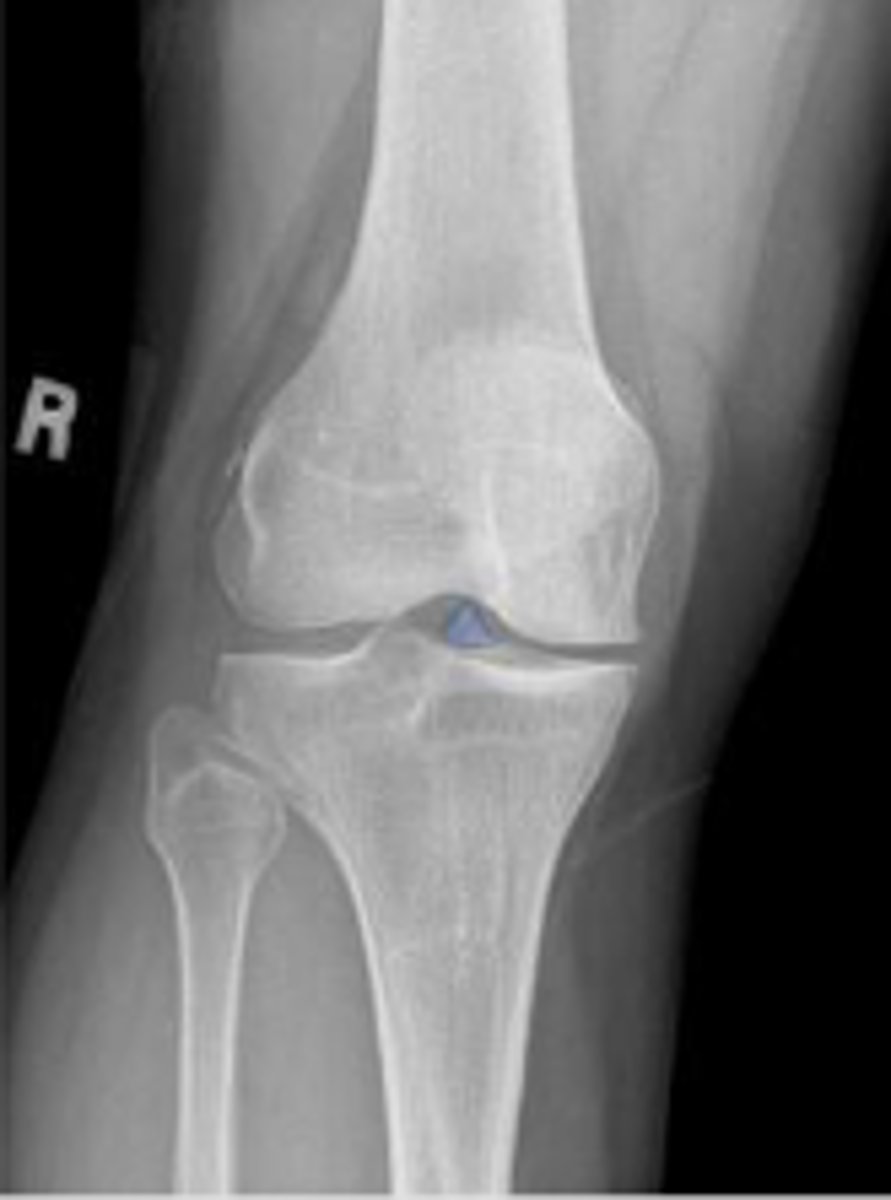

Right AP knee

What is the name of the radiographic view?